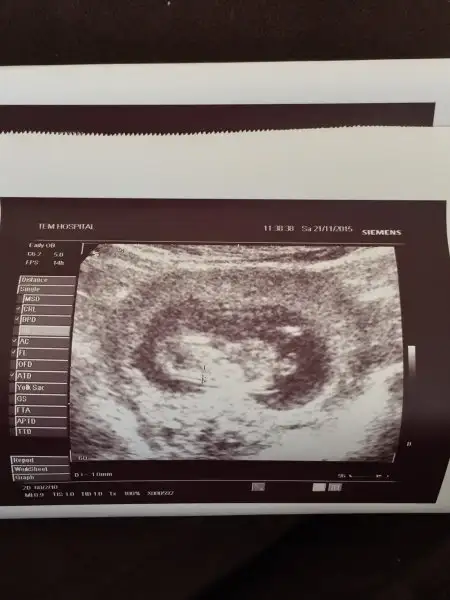

Kızlar Merhaba benim 2 li testteki ultrason görüntüm bu :) doktorum biraz garantici cinsiyet tahmini bile yapmadı merak içersindeyiz. :) acaba kızmı erkek mi ? Rabbim sağlıklı nasip etsin tabide alışveriş içinde önemli cinsiyet :) tahminleri alırsam çok sevinirim.

Sen hangi hastanede yaptırdın ultrasonu? Yanlış anlama, biraz kalitesiz gibi. Valla ben kolunu bacağını kafasını Falan anlamadım

İstanbul tem hospital de yaptırdım net değil çnkü çikolata yemiştim sürekli hareketliydi oyüzden net yakalamadı. inşallah 1-2 haftaya öğreniriz. :)